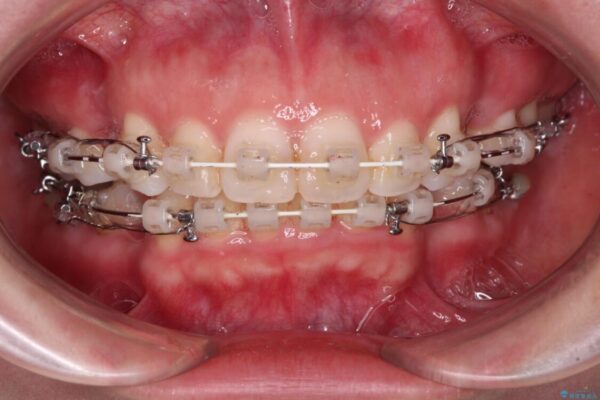

治療途中

• 【モニター】出っ歯と咬み合わせを改善 ワイヤー装置の抜歯矯正 治療途中画像

奥歯の咬み合わせ改善には1年ほどの期間と処置中の噛みにくさを強いることとなりましたが、抜歯後はスムーズに治療を完了させることができました。

歯ぎしりの際に奥歯が干渉していた咬み合わせも理想的な状態に改善できました。